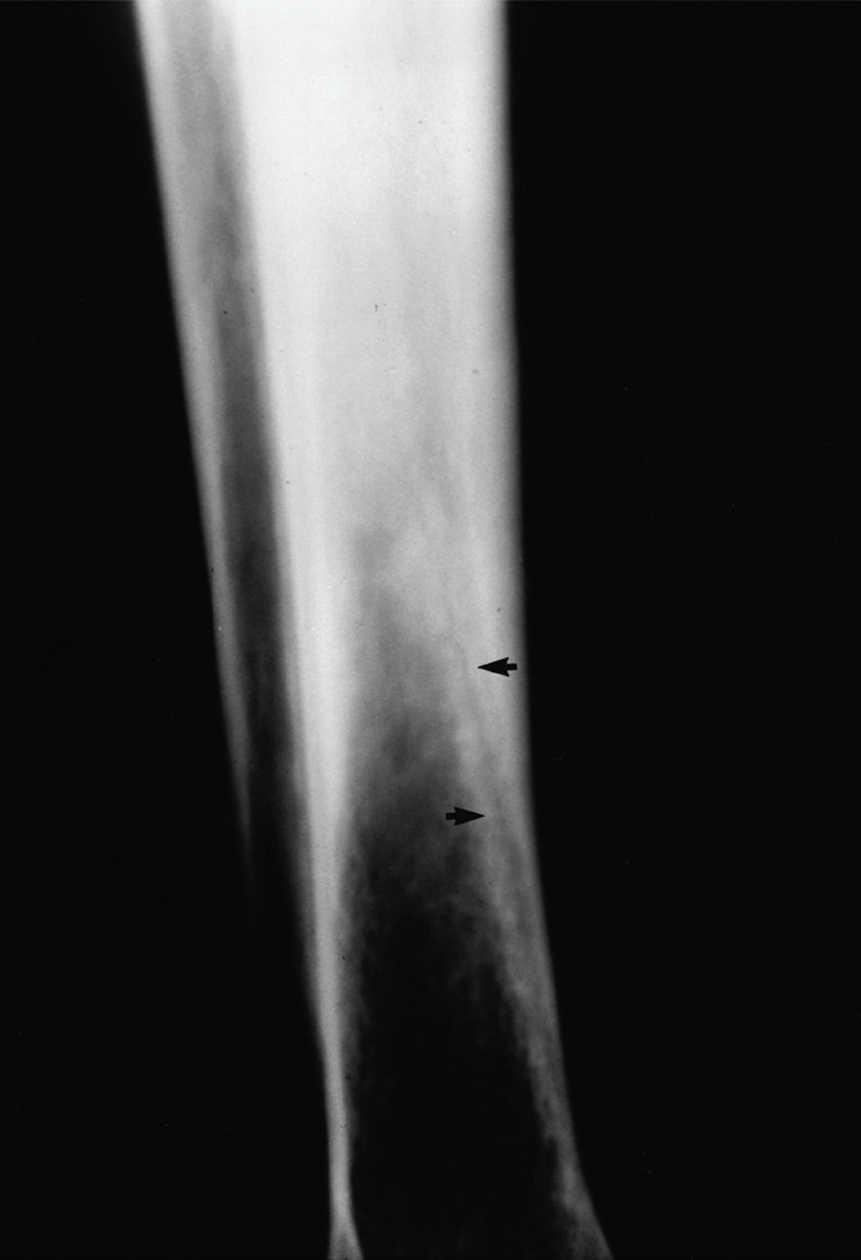

Figura 1. Radiografía simple de tibia izquierda. Se aprecia una línea de fractura longitudinal (flechas).

Se realizó una radiografía simple de tibia izquierda donde se apreció una imagen radiolúcida lineal de disposición longitudinal (fig. 1). La gammagrafía ósea con tecnecio (fig. 2) mostró una hipercaptación fusiforme del trazador en los dos tercios inferiores de la tibia izquierda compatible con una fractura de estrés. La resonancia magnética nuclear (RMN) de tibia, realizada semanas más tarde, confirmó la presencia de una fractura longitudinal de tibia ya en fase de resolución.

Aunque la radiología convencional desempeña un papel importante en el diagnóstico de estas fracturas, el resultado de ésta suele depender de la localización de la fractura y del tiempo transcurrido hasta la práctica del estudio9. Así, al inicio de los síntomas el estudio radiológico puede ser normal. En la diáfisis de los huesos tubulares se ven una o más áreas lineales o circulares radiolucentes en la cortical asociadas con engrosamiento cortical perióstico y endóstico. En las epífisis y las metáfisis y en el hueso trabecular el hallazgo típico es la esclerosis focal9. La gammagrafía ósea con radioisótopos de tecnecio posee una mayor sensibilidad diagnóstica mostrando una hipercaptación de la zona de fractura en las primeras 48 horas, que puede ser suficiente para el diagnóstico ante una clínica compatible8.